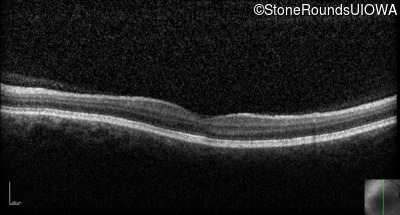

Optical Coherence Tomography - Right - 20/160 -1

Exemplar / OCT Stack